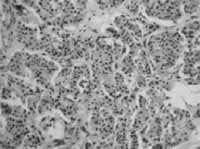

Figura 2. Tumor carcinoide bronquial típico, de localización central.

Es poco frecuente y solo representa del 0.5 al 2.5% de las neoplasias pulmonares (1,3,5,8), con un total de 2000 casos nuevos por año en los Estados Unidos (7).

Si bien en algunas series se demuestra un predominio en algunas series por el sexo femenino (1.2:1.0), y en otras , como la de Torres y cols han demostrado predominancia en el sexo masculino (10) estos últimos más relacionados a los carcinoides atípicos (1), se acepta que tiene una incidencia igual en hombre que en mujeres (3,8).

Se ha descrito como edad promedio de presentación a los 50 años y un rango de edades entre los 12 – 82 años (2), variando la edad de presentación un poco dependiendo del tipo de tumor, siendo el carcinoide típico en la quinta década de la vida, y el atípico con un pico en la sexta década de la vida (5).